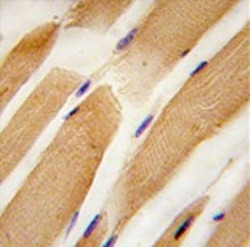

AP11506PU-N IHC

Full details

Method: